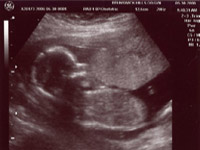

Head shot of the little man |